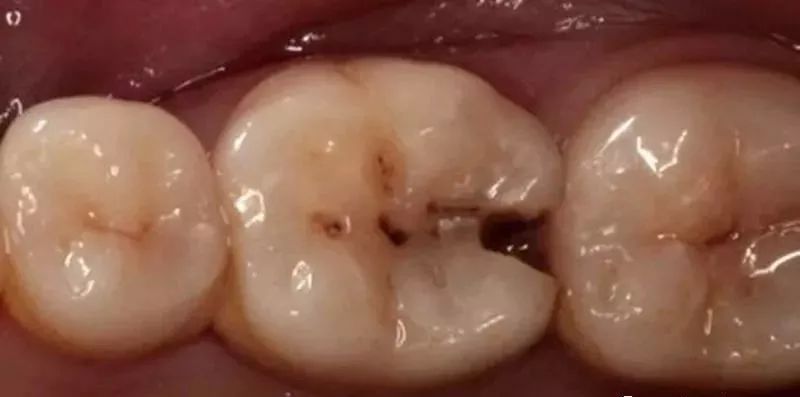

3、塞牙容易让你患龋齿,很多塞牙,都是会导致龋齿的。

1、邻面的龋齿破坏了正常的牙齿结构,造成了缝隙的出现。